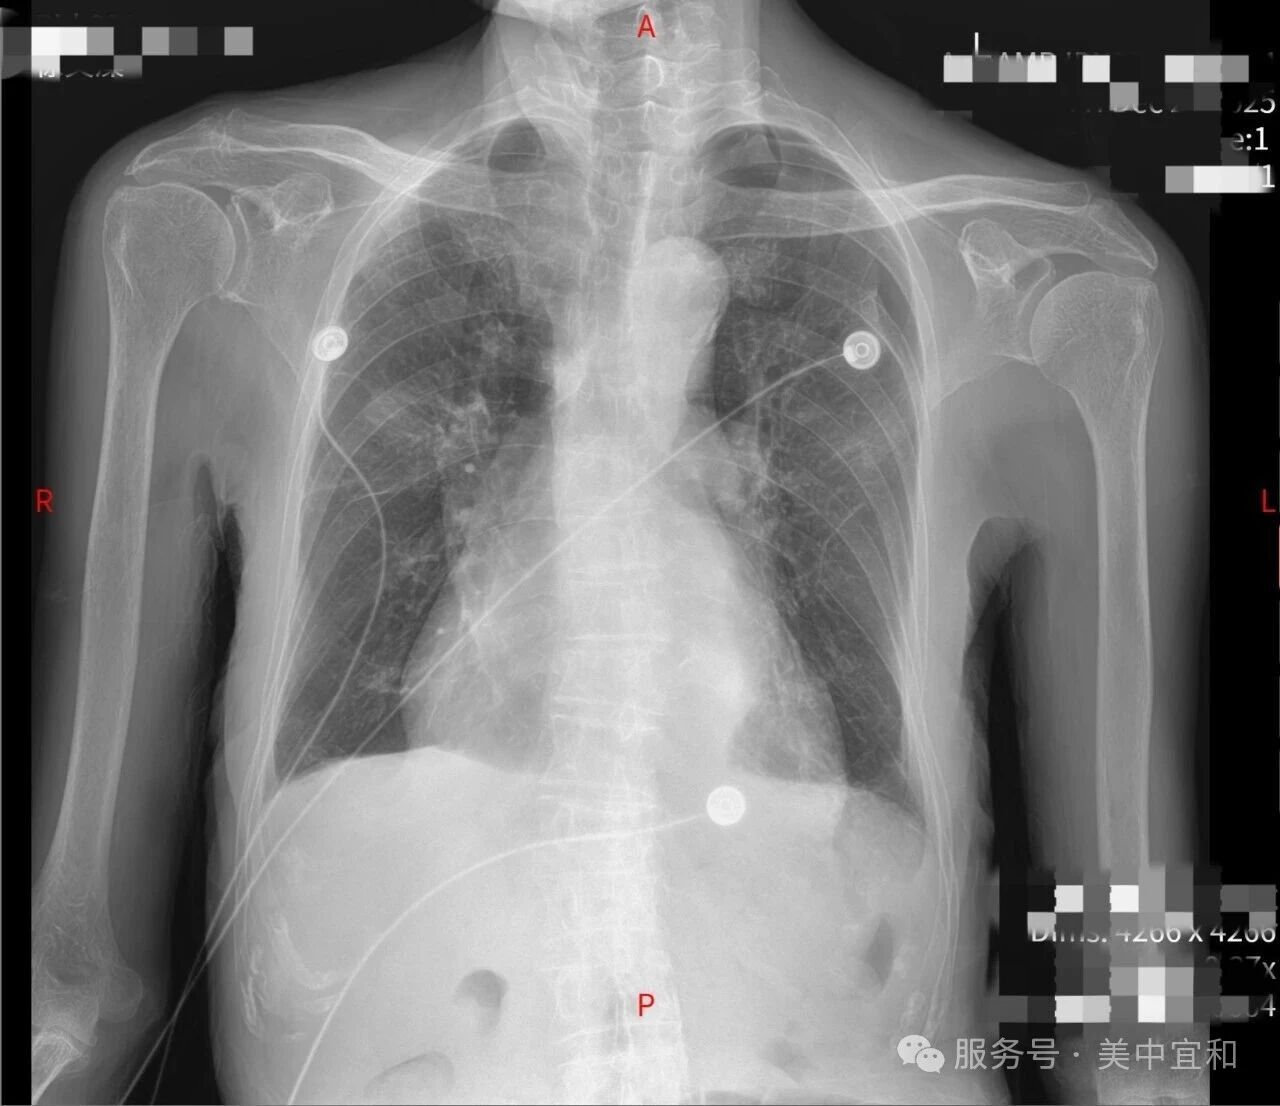

「急救不耽误专科、专科不脱离监护」,经过连续 4 天的治疗和监护,患者心衰指标、呼吸指标、感染指标均有明显好转,最终安返普通病房,目前已经顺利出院。